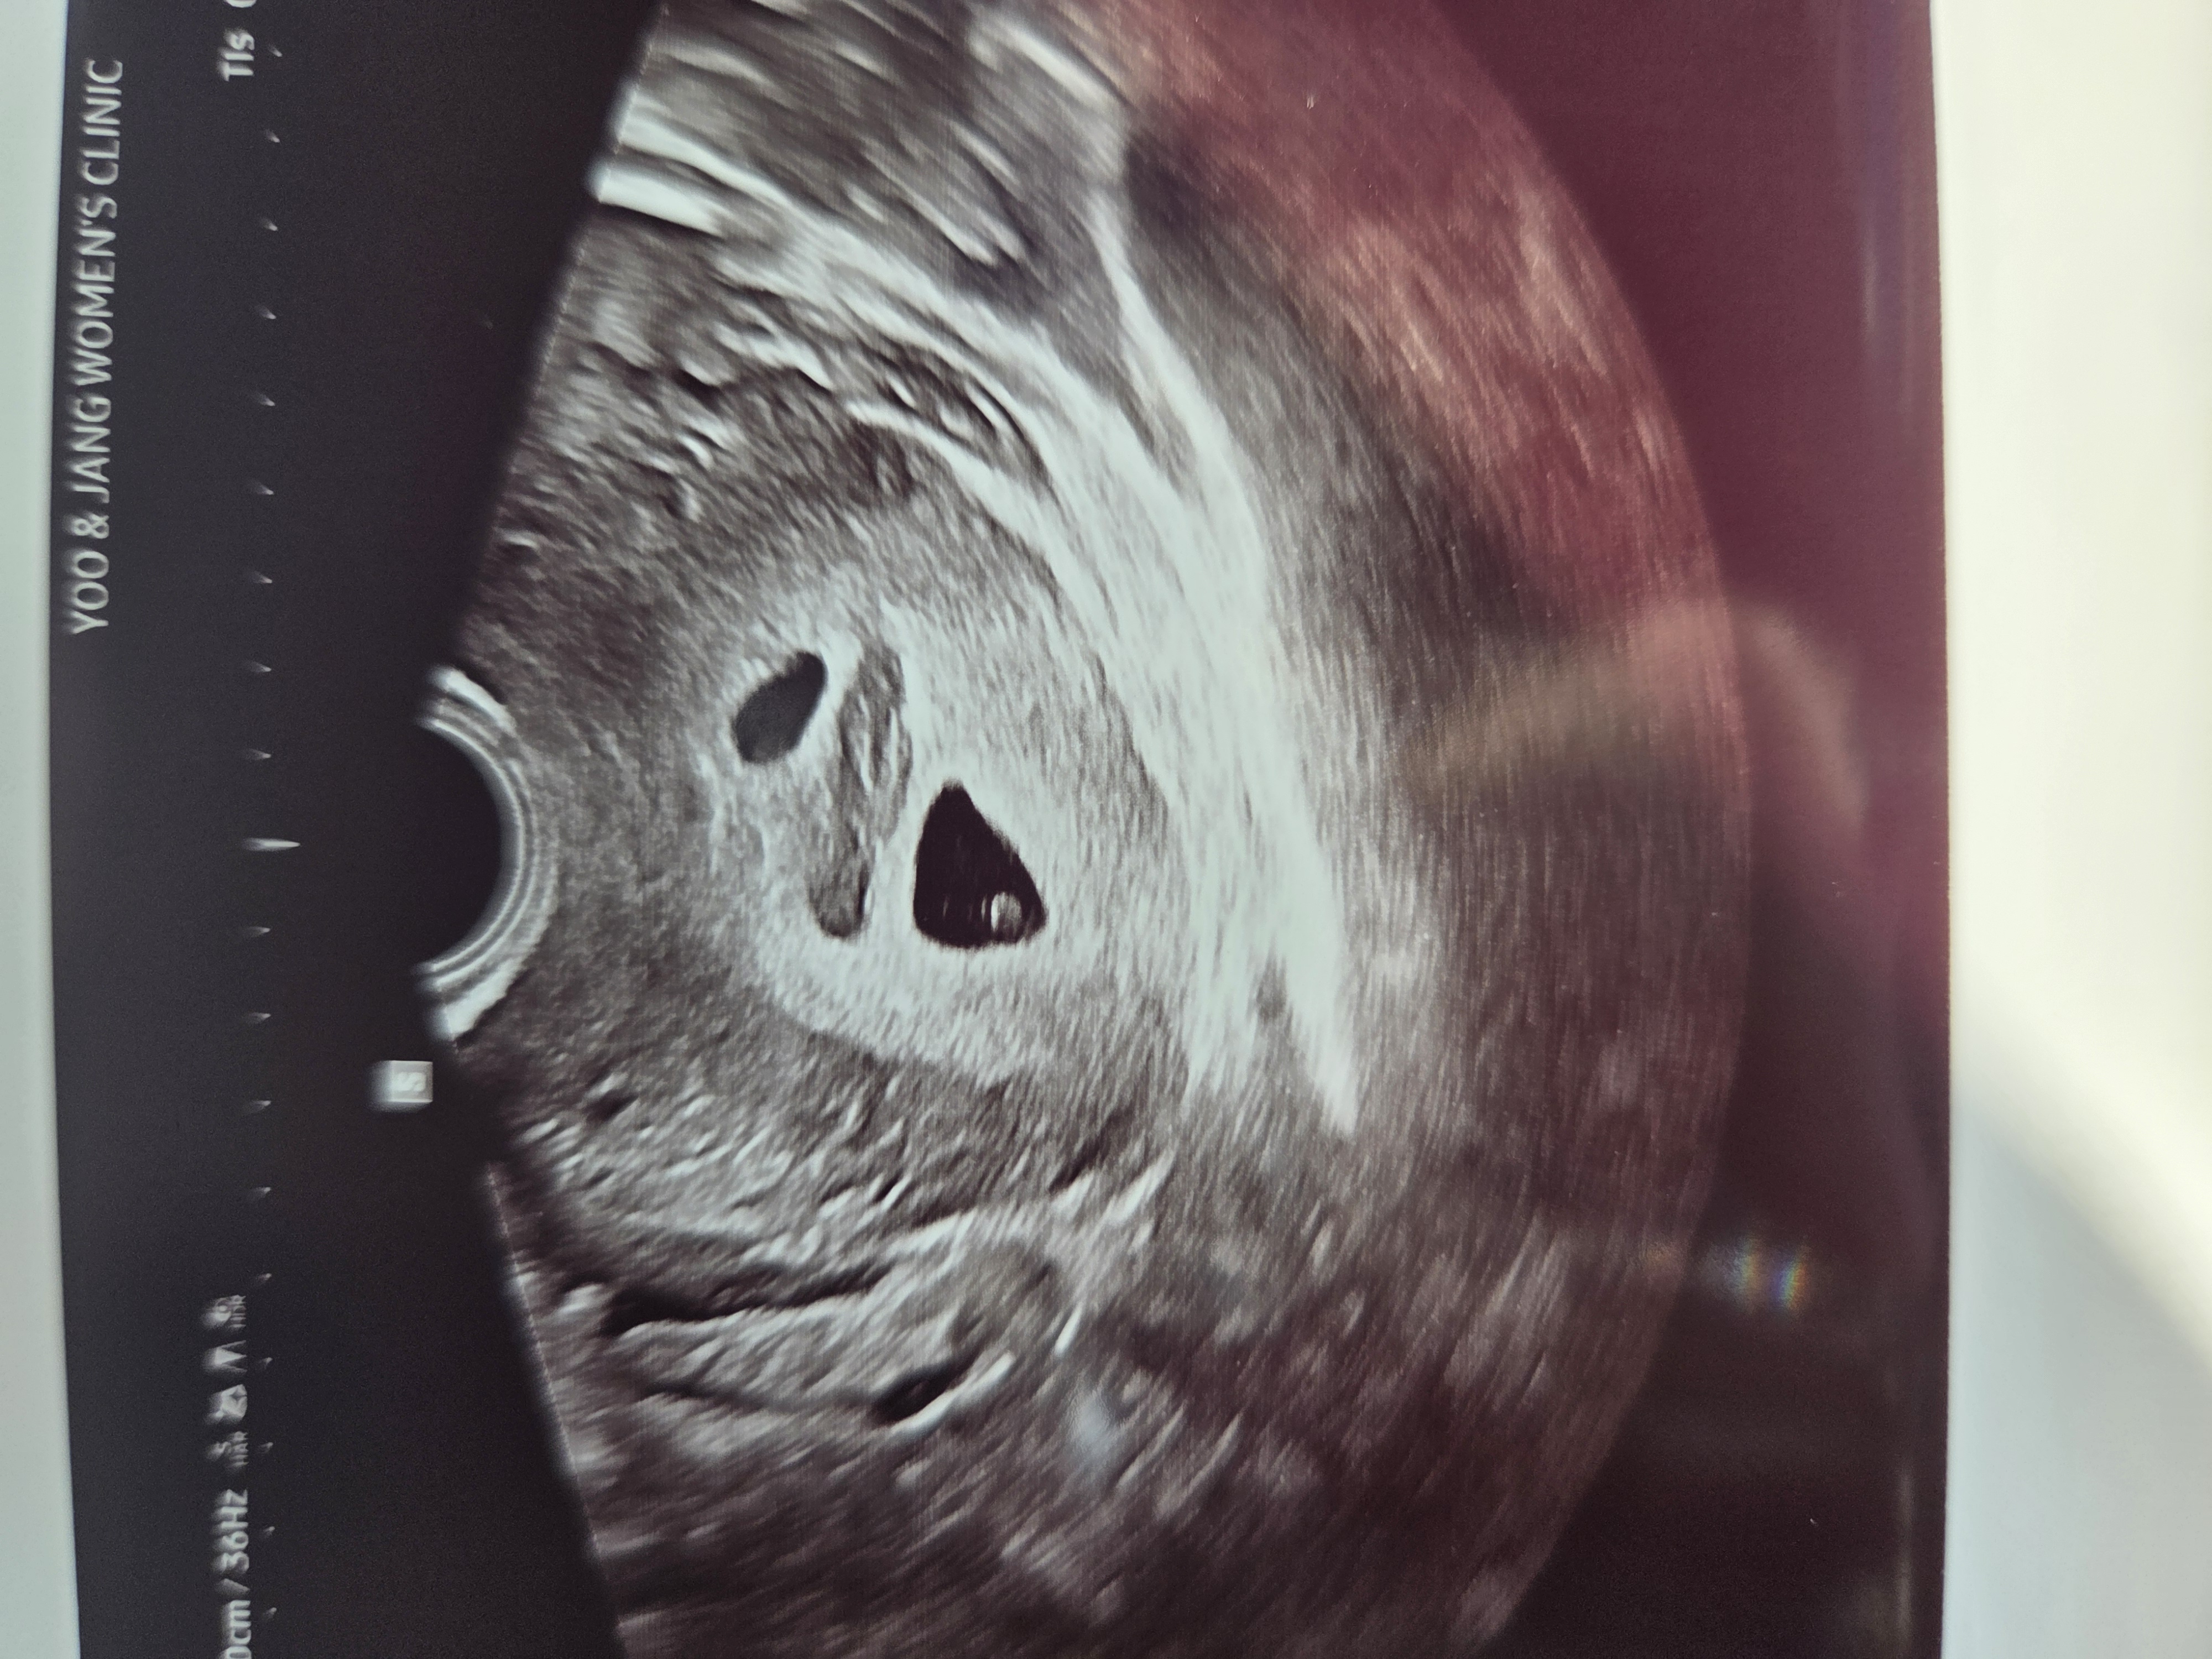

늦은 나이에 결혼하고 3년만에 가진 아이입니다. 마지막으로 자연임신 계획하고 다음부터 시험관을 생각했는데 정...